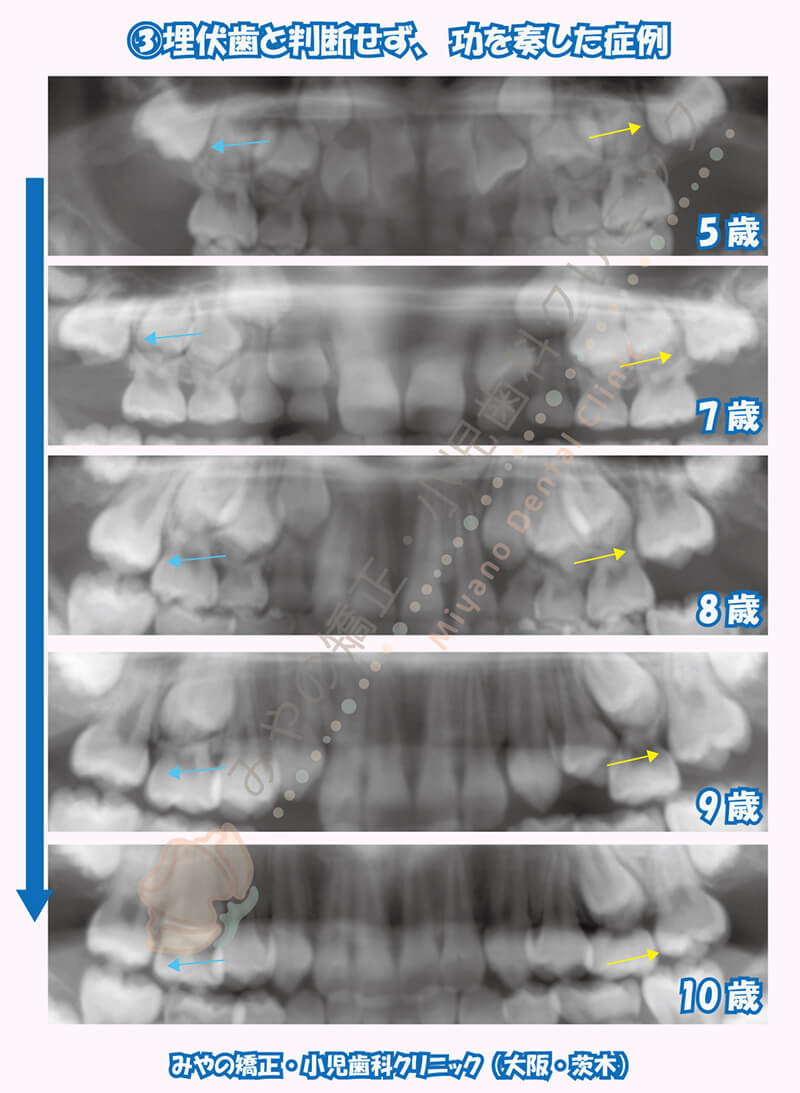

5歳の時点から定期検診を行っていた患者様です。6歳臼歯が7歳の時点でまだまだ生えそうにない位置にいたので経過観察を続けました。8歳の時点で片側の6歳臼歯が生えてきましたが、反対側の6歳臼歯はまだ生えてきていませんでした。ただしレントゲンの変化から生えてきている傾向があると判断し経過観察を継続しました。9歳の時点で萌出まであと少しのところまで変化しており、10歳のレントゲンにてきちんと生えてきていることがわかります。

埋伏歯の牽引治療は本人の負担も大きくできるだけ避けたい治療です。経過観察をすることによるリスクとメリットを天秤にかけ判断していきます。